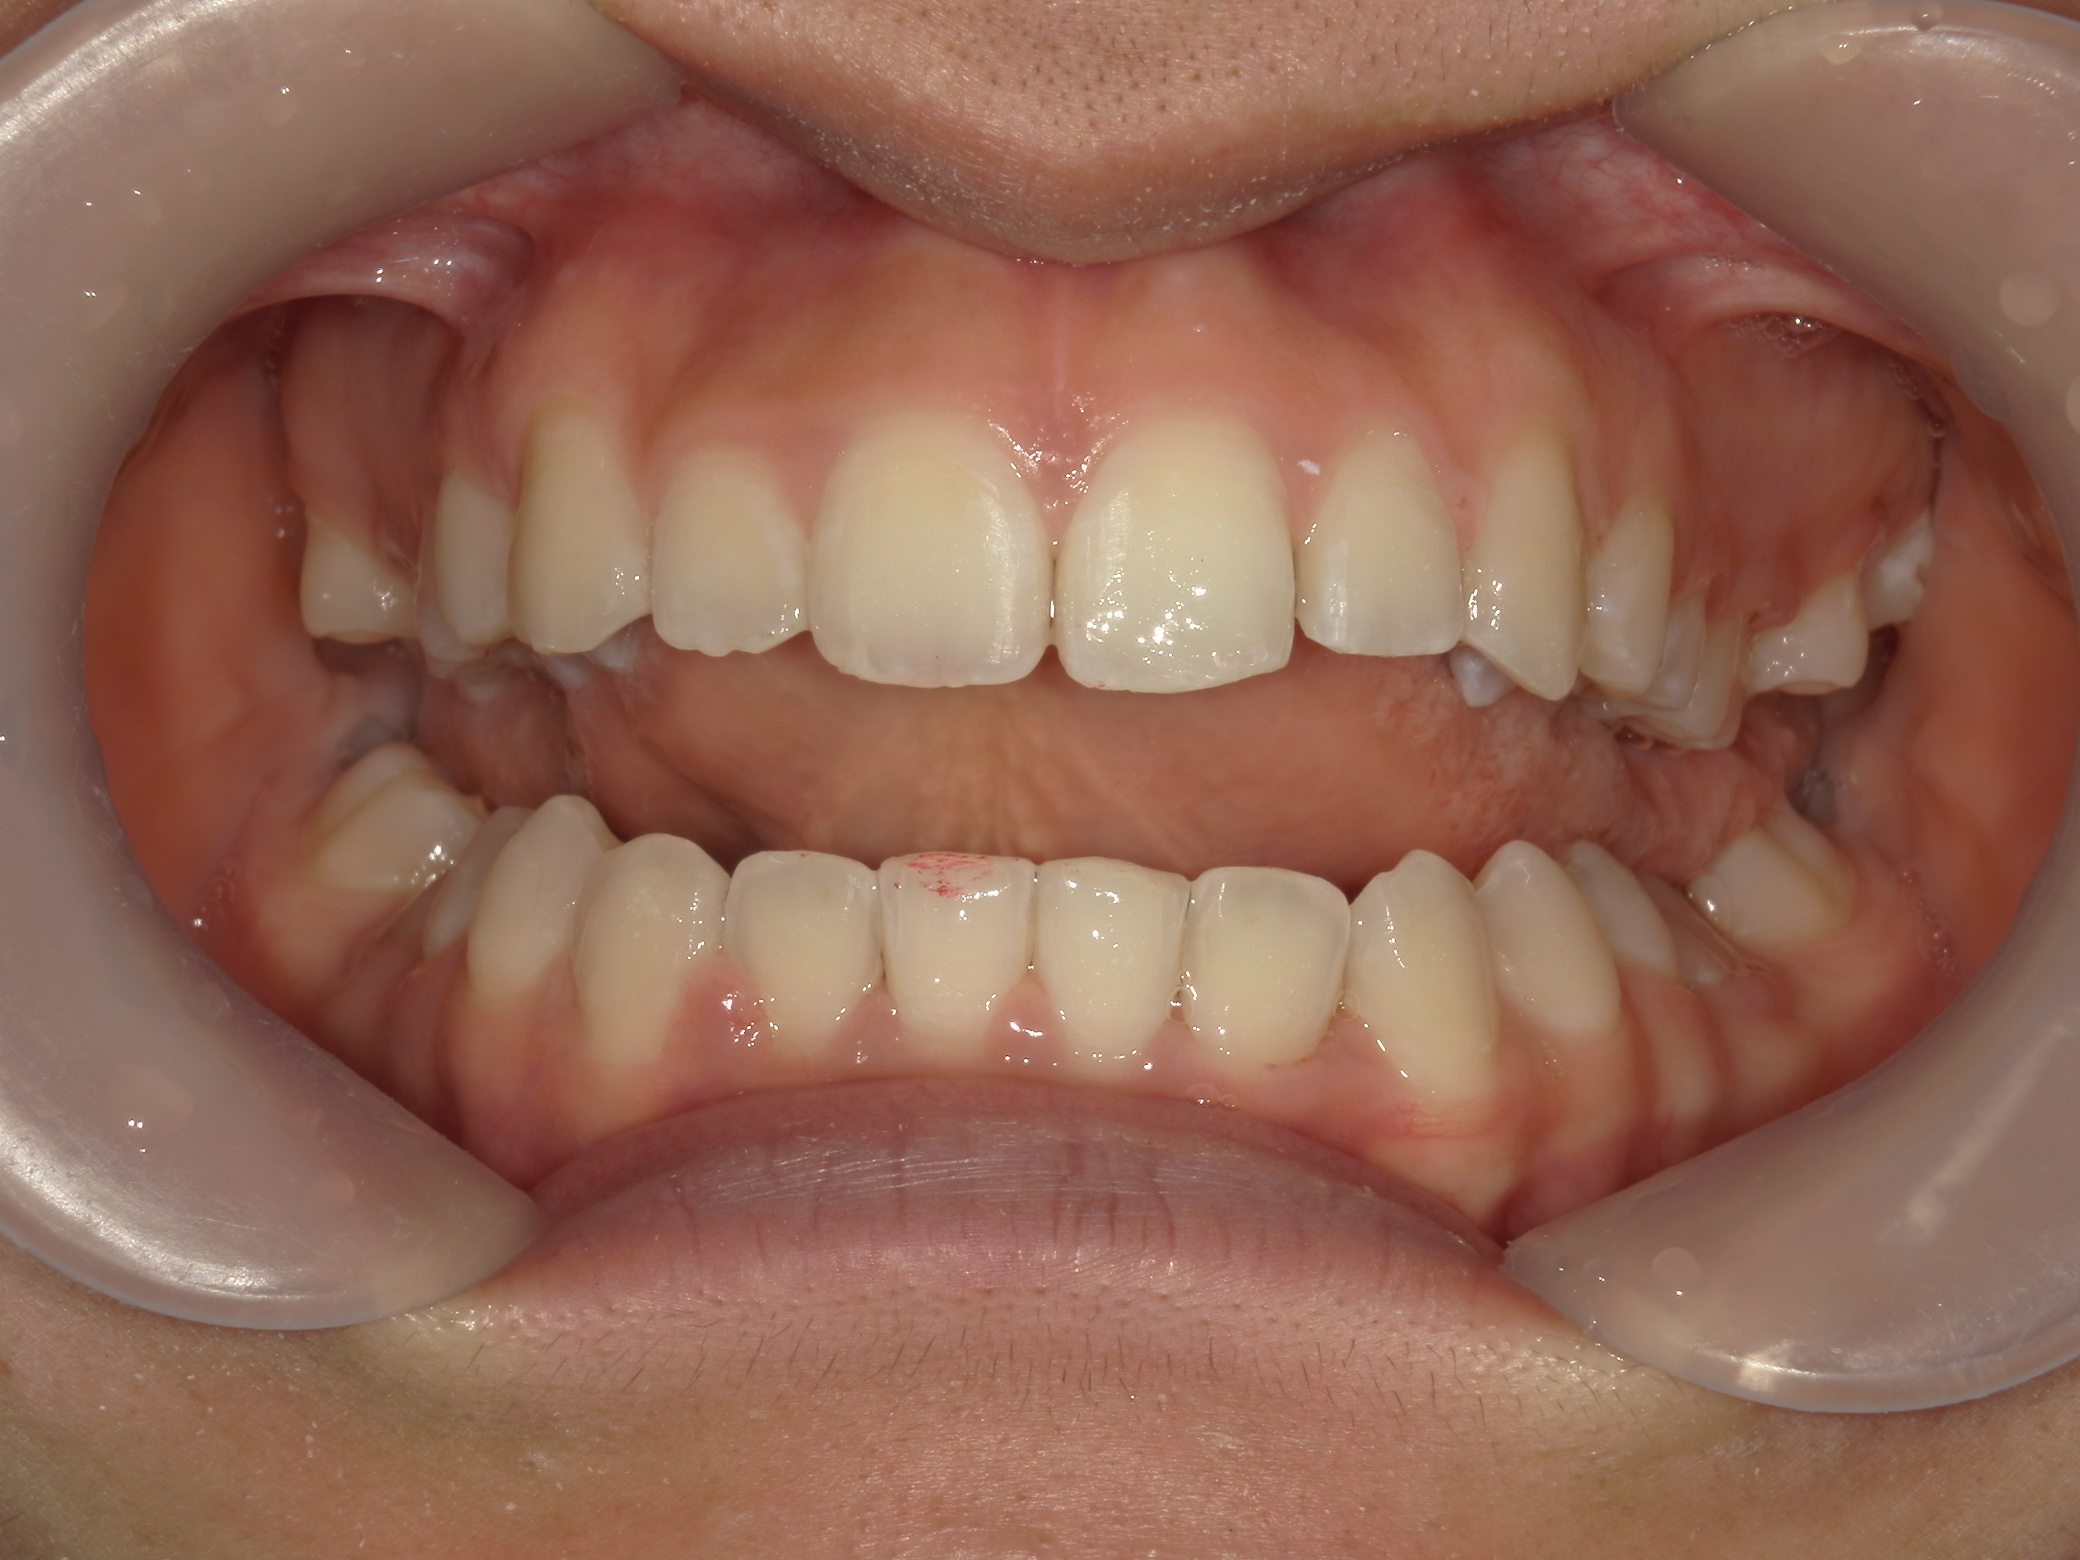

プチワイヤー矯正 症例(54)

主訴: 歯並びが気になる。

ミニインプラント(2本)、スライスカットを併用。

カテゴリー : ガタガタ(叢生)